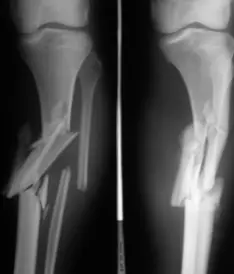

| Compartment Syndrome | Increased pressure within a closed fascial compartment, leading to reduced tissue perfusion, hypoxia, and irreversible muscle and nerve damage. Causes: Fractures (especially tibia/forearm), severe soft tissue trauma, arterial injury, burns, tight casts/dressings, post-ischemic reperfusion swelling, IV fluid extravasation, and bleeding disorders (e.g., hemophilia). High-Risk Notes: Pain may be absent in altered consciousness, children (monitor analgesia response), polytrauma, sedated/epidural cases, or concomitant nerve damage. Open fractures do not always decompress pressure. Gross/Clinical: -tense, shiny leg swelling with blisters in compartment syndrome.Imaging: - Intraoperative fasciotomy | History/Symptoms: Pain out of proportion to the injury (e.g., a “bursting” sensation), which is not relieved by analgesia. Clinical Features (The 5 P’s): - Pain with passive stretch (early, key sign; e.g., ankle dorsiflexion for leg, wrist for forearm). - Paresthesia (early). - Palpable tense swelling (shiny skin, blisters: clear=mild, serosanguinous=severe, bloody=worst; dusky/pallor skin). - Pallor, Paralysis, Pulselessness (late, ominous signs; pulses often palpable until late). Investigations: Primarily a clinical diagnosis (high suspicion key). Compartment pressure measurement can confirm: absolute pressure >30 mmHg or Delta Pressure (Diastolic BP - Compartment P) ≤ 25 mmHg. | Initial: ABCs, supplemental oxygen. Remove all circumferential dressings, casts (bivalve to skin), and splints. Elevate the limb to heart level (not above; higher reduces inflow). Correct any hypotension. Surgical: Urgent Fasciotomy if no response within 1h or confirmed pressure (prophylactic in high-risk like major osteotomy). Release all compartments/skin with long incisions; debride necrotic muscle via 4C’s (early: pink/red, soft, contracts/bleeds on pinch; late: dark, firm, no response); preserve neurovascular. Wound open (bulky dressing/splint, VAC, or boot-lace gradual closure); repeated inspections x48h; coverage in 3-5 days (skin graft usual; flap if nerves/vessels/bone exposed). | Cellulitis, Deep Vein Thrombosis (DVT), Arterial occlusion, Severe soft tissue injury without compartment syndrome; equivocal cases in polytrauma. | Complications: Volkmann’s ischemic contracture (permanent deformity, weakness, sensory loss, chronic pain). Contraindications (Fasciotomy): Confirmed >48h (irreversible damage, high infection risk from dead tissue); crush injuries with already necrotic muscle. |

| Open Fracture | A fracture with a breach in the overlying skin and soft tissues, creating communication with the external environment. All open fractures are considered contaminated (even small punctures; aka compound fracture). Causes: Can result from high-energy trauma (RTAs, falls, firearms; signs: degloving, crush syndrome, bone loss, segmental) or low-energy trauma. Contamination risk higher with farm/soil injuries, bites, delayed presentation (>12h), fecal/oral/soil/water exposure. Mechanism: Low/high velocity missiles (cavitation >300 m/s); in-out (cleaner) vs. out-in (dirtier). Gross/Clinical: ![]() | History: Mechanism of injury (energy, time, place, type/impact method), consciousness, wound size/bleeding amount, other injuries (often missed), tetanus status. Assessment: ATLS protocol (ABCDE) first (treat patient, not fracture; exclude shock/brain injury, monitor vitals; viscera exam: ribs=lungs/liver/spleen, pelvis=bladder/urethra). Examine wound (look/feel/move carefully post-splint), check distal neurovascular status, compartment syndrome. Photograph/remove gross contamination; cover with saline dressing. Classification (Gustilo-Anderson): - Type I: <1 cm wound, clean, minimal soft tissue. - Type II: >1 cm wound, moderate soft tissue (no stripping). - Type IIIA: Extensive soft tissue damage, but adequate bone coverage. - Type IIIB: Extensive soft tissue loss with periosteal stripping; bone exposed, requires flap coverage. - Type IIIC: Any open fracture with an arterial injury requiring repair. | Initial (ER): ATLS first. Cover wound with sterile saline-soaked dressing, splint limb, IV fluids (request blood if needed); traction if no distal pulse/deformity. Prophylaxis: Tetanus prophylaxis/serum and broad-spectrum IV antibiotics immediately (culture tissue/blood); clean major contamination. Surgical: Urgent debridement/irrigation within 6-12h (“Dilution is the solution to pollution”; pulse-irrigate 3-6-9L saline; excise non-viable tissue/foreign material, trim skin edges, remove dead muscle/detached bone, preserve N/V). Stabilization: external fixator (preferred severe; replace with cast post-infection); internal if clean/minimal. Wound closure delayed (primary if small/clean; secondary if contaminated/large). Early soft tissue cover. | The diagnosis is typically obvious. Key: Classify severity; identify associated injuries like compartment syndrome, vascular damage, or high-energy signs (e.g., crush). Differentials for contamination: Primary (field debris) vs. secondary (post-fixation if poor debridement). | Complications: Infection (cellulitis, osteomyelitis, chronic with sequestra/drainage, gas gangrene), tetanus; higher with delay/exposure/bites. - embolisms fat, thrombi others.. Case Insight: Unconscious patient (e.g., open tibia post-RTA): ABCDE/cervical collar, distal pulses/traction, admit for debridement; ankle fall: Splint post-ABC, assess neurovascular. |